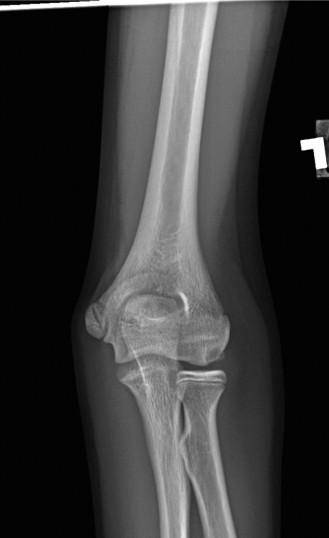

The patient undergoes resection arthroplasty with antibiotic cement spacer and a 6-week course of IV antibiotics. He returns to clinic 4 months later with improved pain, CRP <3, however, on examination he has a positive belly press sign and increased external rotation compared with the contralateral shoulder. Imaging is shown in Figure 2–57.

Figure 2–57

The correct answer is (D). The patient has completed his course of antibiotics and his spacer and is now an appropriate candidate for explanation of the cement spacer with revision shoulder arthroplasty, therefore Choices A and C are incorrect. The patient’s clinical examination findings point to rotator cuff tear (specifically subscapularis) which has occurred in the interval between his obtaining his initial total shoulder arthroplasty and his current examination. Therefore, total shoulder arthroplasty (Choice B) is contraindicated, and the patient should have a reverse total shoulder arthroplasty. Objectives: Did you learn...? Recognize the clinical presentation of a patient with infection after total shoulder arthroplasty?